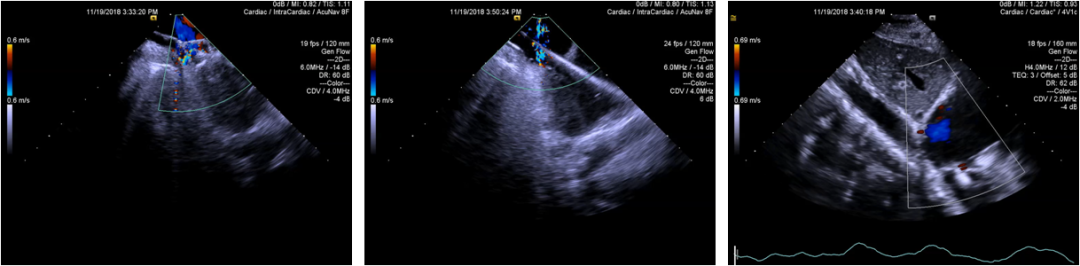

病例资料-Case 1

• BP:140/100mmHg,heartrate:90bpm

• Bloodtest: normal

• ECG: Sinusrhythm, Left anterior branch block

• TEEexcludes left atrial thrombosis

• CAG: LADand RCX are normal; 40% stenosis of RCA

血流动力学参数